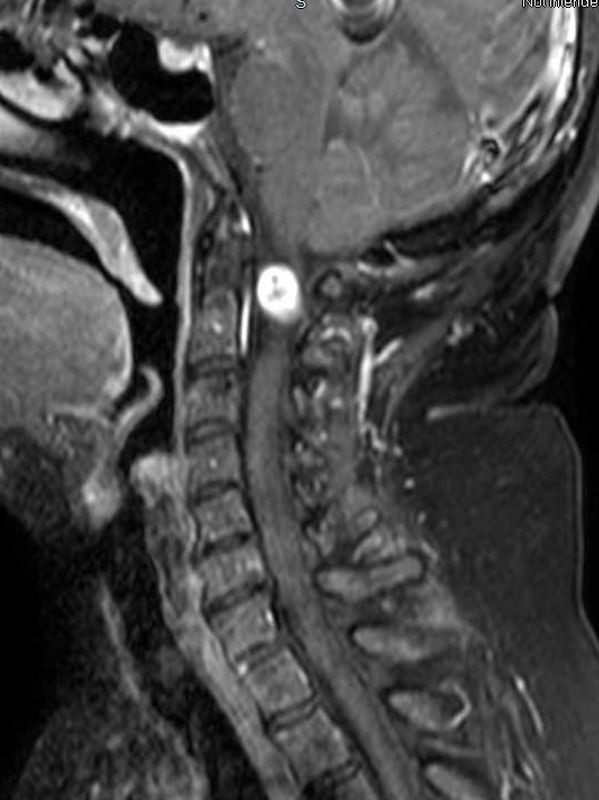

Randy McWilliams describes his neck surgery performed by physician leader, Dr. Farhad Limonadi from Lucent Neuroscience Institute.

Yolanda Maston describes her neck surgery performed by physician leader, Dr. Farhad Limonadi from Lucent Neuroscience Institute.